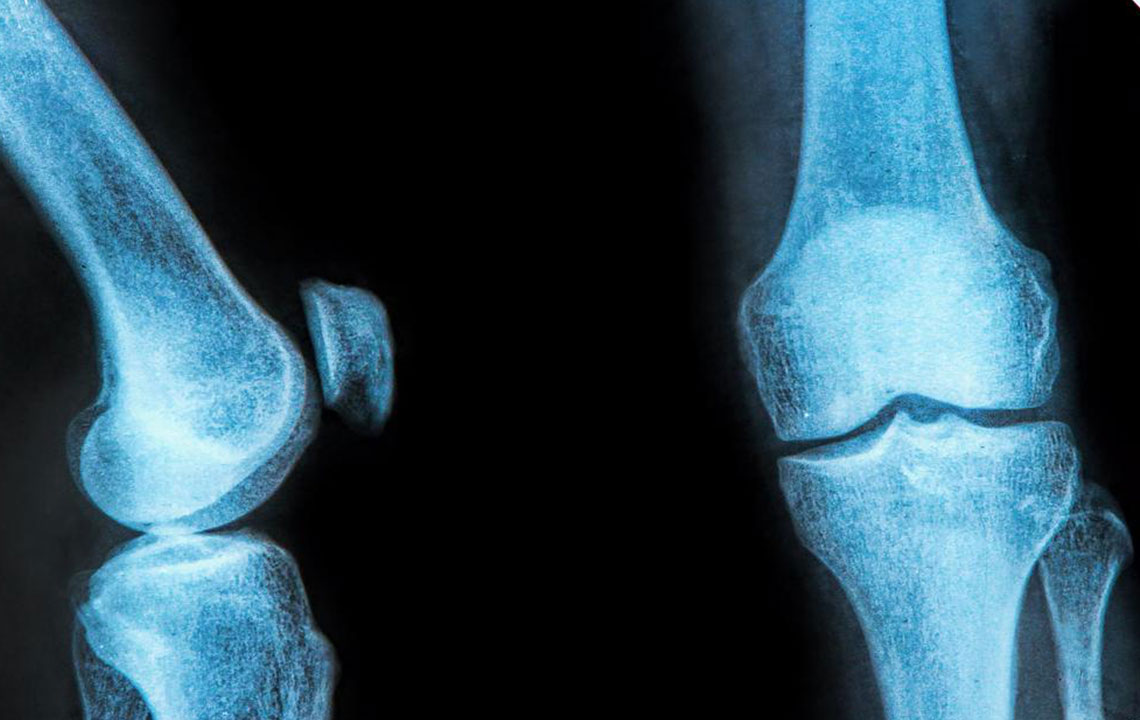

The rubbery C-shaped disc cushioning your knee is a meniscus. There are two menisci in each knee. One at the inner side and the other on the outer side. It is this meniscus that helps to keep your knee steady. It balances your body weight around your knee. If there is a tear in the meniscus, you will experience a lot of pain.